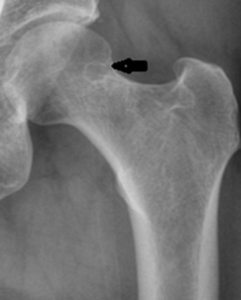

5. Synovial Herniation Pit

This non-pathologic radiolucency is seen in up to 5% of the adult population and is most often asymptomatic, though symptomatic cases have been described. The classic appearance is a round, ovoid, or “8-shaped” radiolucency with a thin sclerotic border most often found at the anterior superior femoral neck, though it can be found in the anterior inferior femoral neck as well. It is formed by a herniation of synovium through a cortical defect of the femoral neck. They are usually 5-mm or less in diameter and are more often found unilaterally than bilaterally.